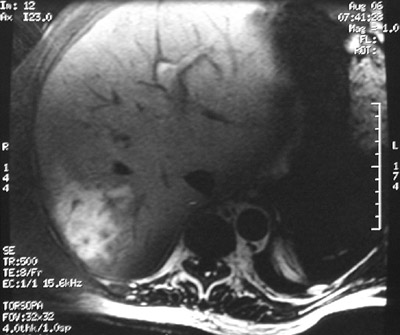

In these T1 weighted abdominal MRI scan views above and below can be seen an area of liver infarction caused by a portal vein thrombosis.